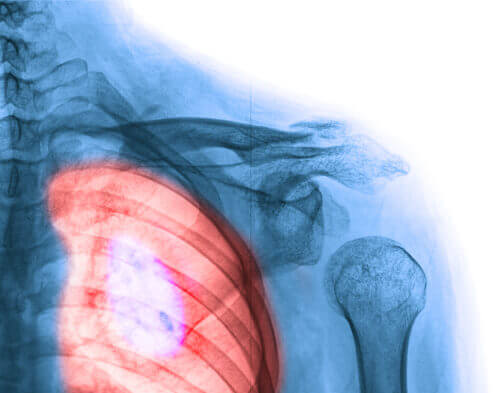

4. Keuhkosyöpä

Tämä on yksi yleisimmistä naisilla esiintyvistä syövistä. Viime vuosien aikana sen esiintymistiheydestä on alettu huolestua, koska sillä on korkein kuolleisuusaste sekä miehillä että naisilla.

80 % keuhkosyövistä saa alkunsa tupakasta. Tupakoinnilla ja passiivisella tupakoinnilla on vakavat seuraukset terveydelle. Sitä on ehdottomasti vältettävä, kuten myös muita huonoja tapoja, jotka johtavat moniin sairauksiin.

Tupakoivien naisten määrä on lisääntynyt huomattavasti maailmalla. Joko mainoskampanjoista puuttuu jotain olennaista tai viesti vain ei ole mennyt perille: Lopeta oman terveytesi ja mielenrauhasi vuoksi! Pidä silmällä seuraavia oireita: